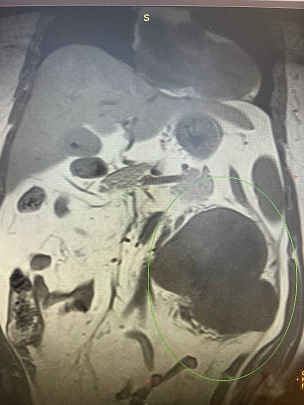

57-летняя женщина поступила в Коломенскую больницу с острой болью в левом боку и примесью крови в моче. При проведении диагностических исследований была выявлена крупная опухоль почки, которая занимала всё забрюшинное пространство слева и часть брюшной полости. Ситуация осложнилась ещё одной диагностической "находкой" – единичным метастазом опухоли в лёгких.

В результате нефрэктомии пациентке удалена опухоль левой почки размером 25 см и весом примерно 3 кг. Уже спустя пять суток после операции женщина была выписана из стационара и направлена для проведения противоопухолевой терапии в Центр амбулаторной онкологической помощи Коломенской больницы.